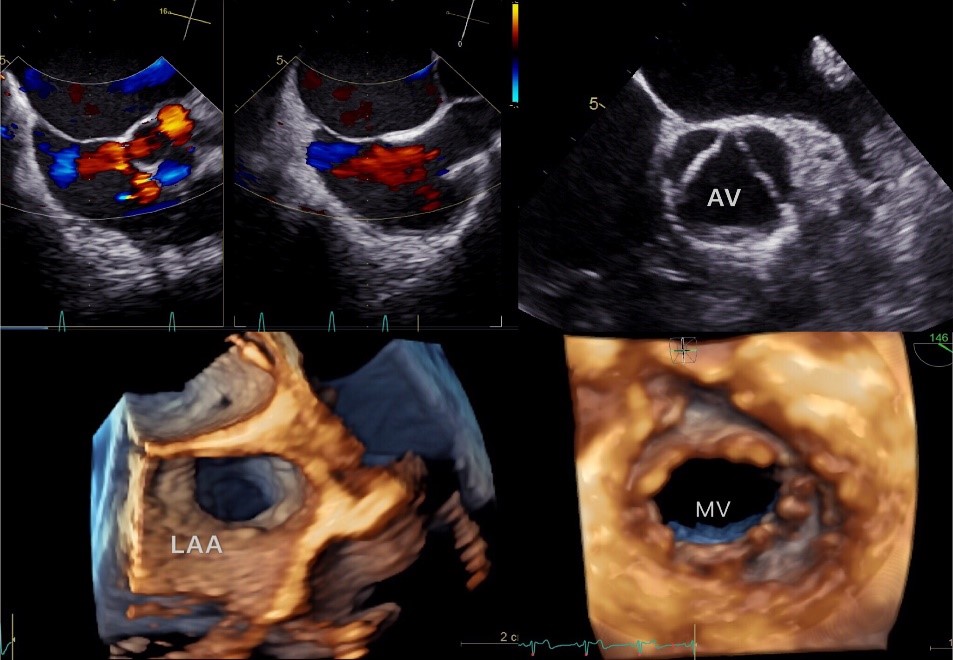

简单来说,经食道超声心动图是将超声探头置于食道内,从心脏后方近距离探查其深部结构。许多经胸壁超声心动图观察不清晰的病例,特别针对左心耳内有无血栓、卵圆孔未闭、瓣膜病及瓣膜赞生物以及心脏或部分危重病人术中监测等,亦用于评估、评价手术方式及效果等方面的应用。此检查方法,较传统经胸超声心动图提高了心血管疾病论断的敏感性和可靠性。从事此项技术的医生均经过北京安贞医院学习培训,并具备独立工作能力。所使用设备为GE Vivid E95彩超仪,拥有业内最为精巧的经食道容积超声探头6VT-D,融合了高密集信息处理及头端微型波束形成器技术,在减小探头体积的前提下,实现经食道单一心动周期快速四维成像的冋时更提高了患者的耐受性,比传统二维图像更直接、更真实,具有更丰富的诊断信息。